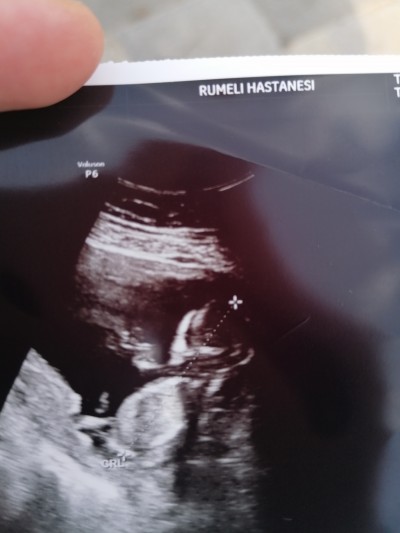

çıkıntı var erkek gibi dedi değişir mi acaba 14 haftalık

Ya çıkıntı sını bende gördüm oda erkek dedi çıkıntı var Ama kesin olması için 2 hafta sonra gel dedi. Bence gitme canım en az 15 i bekle böylede muallakta kalıyo insan